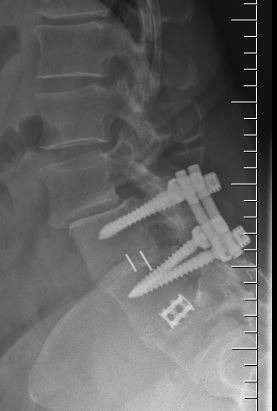

Another example is a young lady who had severe low back pain. Traditionally, fusion surgery through very large incisions would be required. With the new “percutaneous” technique of placement of pedicle screws, we were able to remove her disc through her abdomen and place screws through two small incisions in her back. She is now more than 80% improved.*